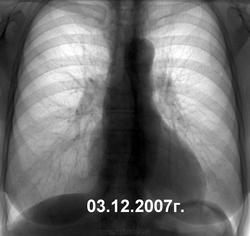

Очередная динамика. На 1-м снимке - на тенюшку не обратили внимания, на 2-м - отправили в онко, был 3-й, но к сожалению потерян в дебрях компьютерной памяти. Со слов пациентки - состоит на учете в тубдиспансере. Может и вылечат?

Мытарства в медицине конституционно бесплатной, а фактически финансово неподъемной для большинства больных выглядят по типу ни в сказке сказать, ни пером описать. Я же честно написал, что на первом снимке - стоит норма, поставленная мною. Но на втором - уже консультация онко. Каким образом пациент оказался на учете в ПТД - одному богу известно. И опять же вопрос, что нужно было делать во-время 1-го снимка, как позиционировать, идентифицировать ту тень?

По характеру развития-онкопроцесс.Игорь Иванович, на первом снимке уже патология.При ретроспективе хорошо видно.Опухоль и к тому-же первичная.Росла ,росла и доросла до мезотелиомы.